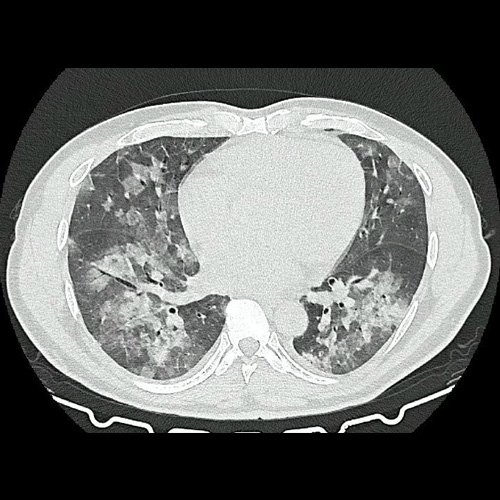

- Tomografía de tórax sin contraste endovenoso (Dia 0):Se observan múltiples áreas de consolidación parenquimatosa con broncograma aéreo y de distribución difusa por ambos pulmones, predominando en los lóbulos inferiores, asociadas a engrosamiento de los septos y rodeadas de tenue vidrio esmerilado. Se identifican estructuras ganglionares lateroaórticas, pretraqueales y subcarinales, ninguna de ellas sin alcanzar rango megálico.

Tomografia de torax sin contraste endovenosos (Ventana pulmonar-corte axial)

Tomografia de torax sin contraste endovenosos (Ventana pulmonar-corte axial)

Tomografia de torax sin contraste endovenosos (Ventana pulmonar-corte axial)